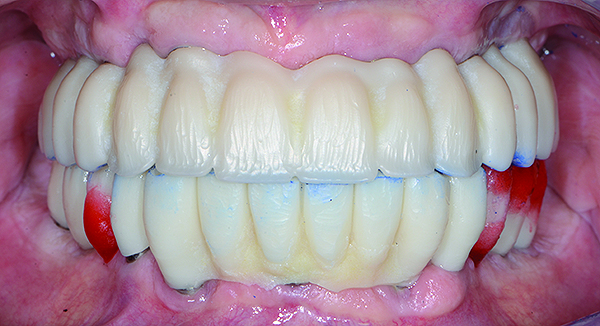

Fig 15. Intraoral frontal view of completed maxillary and mandibular zirconia restorations.

Figure 15

The maxillary prototype was adjusted, polished, and left to function with the mandibular provisional. The definitive maxillary zirconia restoration was then completed from the information provided by the prototype, and the cutbacks for the facial porcelain (Nos. 6 through 11) were done after milling but before sintering. Subsequently, the mandibular prototype was adjusted to the sintered and colored maxillary zirconia framework before the application of porcelain to Nos. 6 through 11 and final glazing (Figure 11). Following this step, the mandibular definitive monolithic zirconia restoration was milled, colored, and sintered. The facial porcelain (Nos. 6 through 11) was applied, and then both maxillary and mandibular restorations were stained and glazed (Figure 12). Both bridges were inserted at the same time (Figure 13 through Figure 15). Minor occlusal adjustments and oral hygiene access was verified and the zirconia surfaces polished. The bridge screws were torqued to 20 Ncm according to the manufacturer’s recommendation, and No. 24 was luted with a provisional cement. Postoperative radiographs were taken (Figure 16).

The patient has been followed for continuing care since completion of the reconstruction and no complications have been reported to date (Figure 17 through Figure 20).